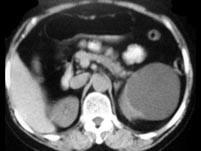

问题 女,55岁,发热,左侧腰部痛胀不适4天,CT检查如图所示,下列说法错误的是 ( )

选项 A、考虑为多囊肾合并感染 B、考虑为多发肾囊肿合并感染 C、病灶境界清晰,囊内密度近似水的密度 D、肾前筋膜增厚 E、左肾上极和下极各可见一个类圆形的囊性病灶

答案 A